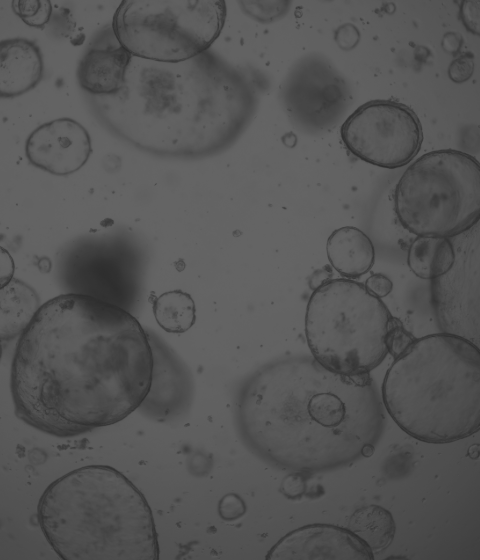

• 類器官培養

廈門模基生物科技有限公司(Xiamen Mogengel)位于中國廈門,是中國首家提供類器官培養整體解決方案的企業;是一家集研發、智造、銷售、服務于一體,致力于3D類器官培養原料的研發與產業化升級的高新技術企業。

公司擁有蛋白表達純化中心、實驗動物中心、類器官研究中心和智能顯微觀察研究中心等四大技術平臺。獲得廈門市“雙百人才”企業、太倉“國際青年創業大賽一等獎”等榮譽。公司已經申請40余項專利。目前公司有基質膠、類器官培養基、細胞因子、類器官培養耗材和智能顯微鏡等產品,已有超過60個科研團隊使用本公司產品發表文章,客戶遍布海內外。